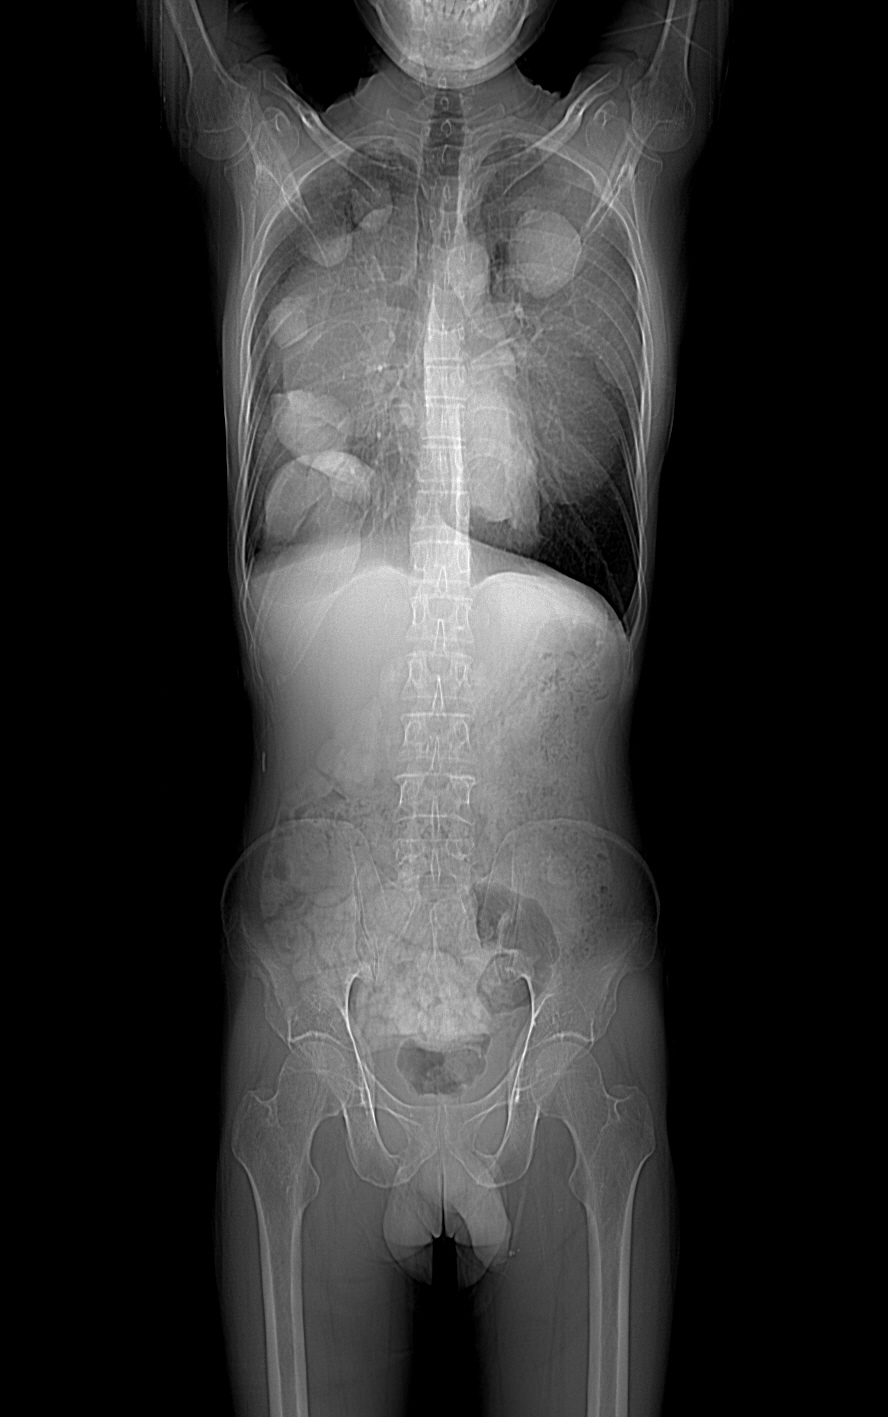

Old X Ray images

HRCT was done on 22 feb 2016